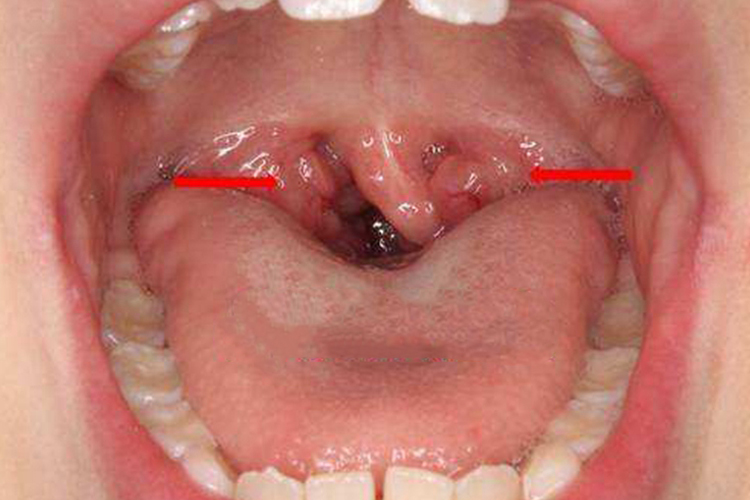

扁桃体二度肥大是指扁桃体超出舌腭弓但未达到中线,可能导致呼吸困难、吞咽障碍等问题,治疗方法的选择取决于病因、症状的严重程度以及患者的年龄和健康状况等因素,需要使用非手术治疗、免疫疗法等。